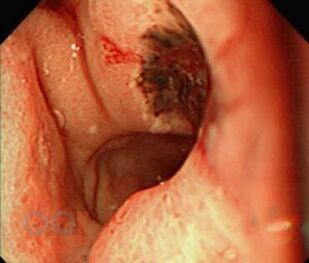

Вторая части учебного пособия «Осложнения язвенной болезни желудка и двенадцатиперстной кишки» посвящена язвенным желудочно- кишечным кровотечениям. В настоящем пособии освещены вопросы этиологии и патогенеза острых желудочно-кишечных кровотечений, их классификация, клиническая картина, современные методы диагностики. Подробно изложены принципы консервативного, эндоскопического и хирургического лечения данной патологии.